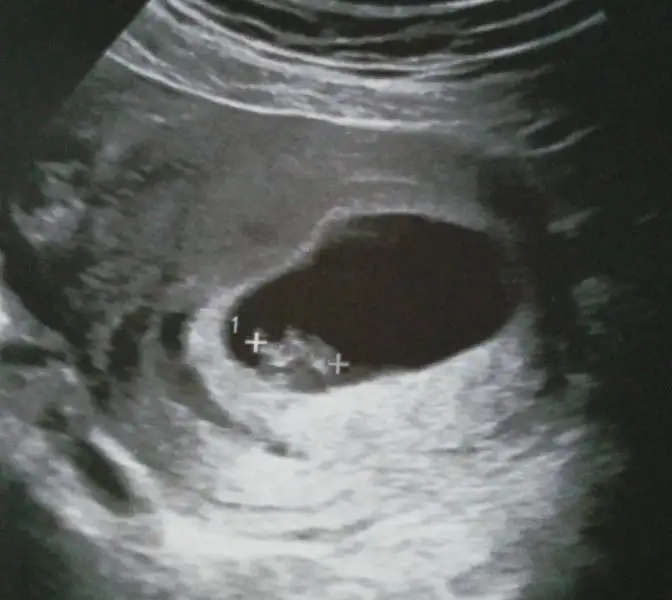

Merhaba 7. hafta görüntüsü benimde. Yorumlarsanız sevinirim :)